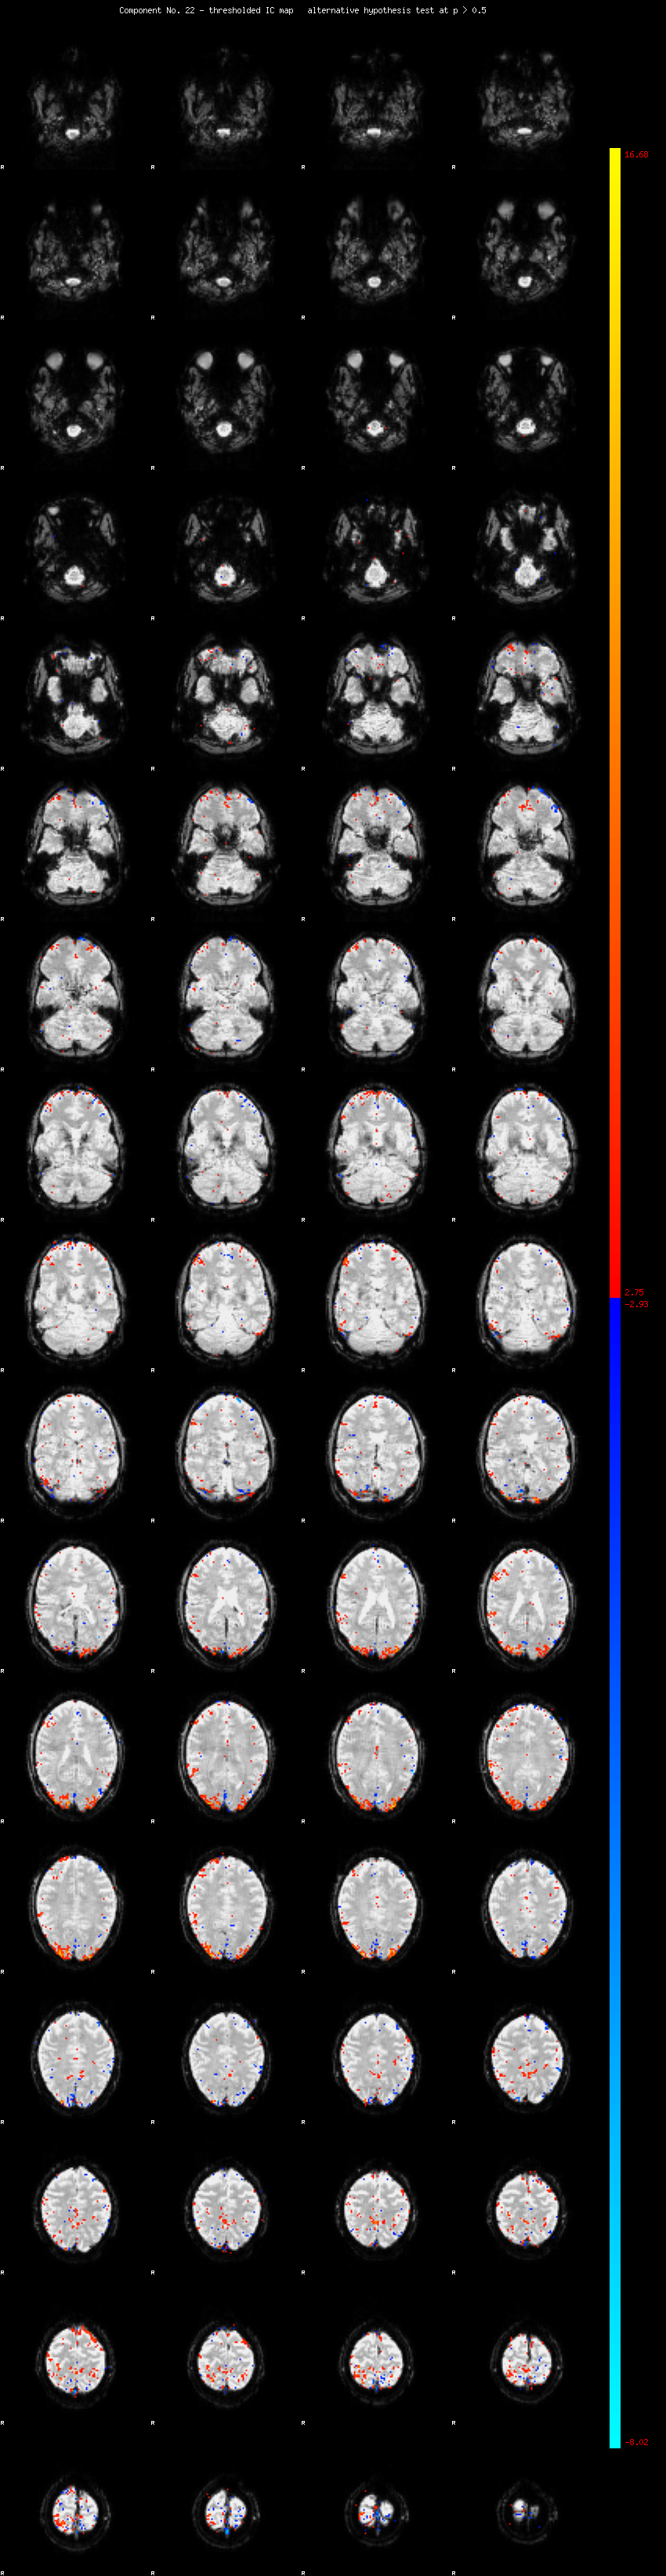

MELODIC Component 22

1.31 % of explained variance;     0.87 % of total variance